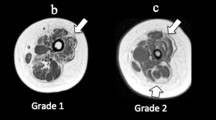

Physical characteristics of subjects in the BSCP and TD groups are summarised in Table 2. There were no group differences in age, body mass, height, or BMI (p > 0.05). The GMFCS level of the BSCP subjects are also presented in Table 2. The average standard deviation representing reproducibility of intramuscular fat averaged across all muscles was 0.33%.Figure 2 shows a histogram of group-averaged percentage IntraMF and IMAT. The BSCP group had a significantly higher average percentage IMAT (p < 0.001) and IntraMF compared to the TD group for all muscles investigated (p < 0.001), with the soleus having the largest percentage fat difference (12.9% greater in BSCP group). In the BSCP group, IntraMF was significantly correlated between all muscles measured (r = 0.697 to 0.947, p < 0.001 to p = 0.025) except for the soleus, which did not correlate with any other muscle (r = 0.437 to 0.587, p = 0.074 to 0.206). Figure 3 shows a histogram of group-averaged SF/M ratio. The mean SF/M ratio was 1.9 times greater in the BSCP group compared to the TD group; however, this difference was not statistically significant (p = 0.179). Example images for a case and age-matched control are given in Figure 4.

One-way ANOVA and post hoc analysis revealed significant differences in IntraMF levels by GMFCS level (p < 0.001), with GMFCS level III significantly higher compared to GMFCS levels I and II (p < 0.001 and p = 0.001 respectively). No significant difference was observed in IMAT or SF/M with GMFCS level (p = 0.131). In the TD group, SF/M was correlated with IMAT (r = 0.81, p = 0.005) but not with IntraMF (r = 0.182, p = 0.206), and no correlation was observed between IMAT and IntraMF (r = 0.251, p = 0.079). In the BSCP group, no correlations were observed between SF/M and IMAT (r = 0.392, p = 0.262) or IntraMF (r = 0.134, p = 0.353); IMAT and IntraMF were significantly correlated (r = 0.529, p < 0.001).

We conducted MRI measurements of IMAT, SF/M ratio, and IntraMF on 10 young adults with BSCP and 10 of their TD peers. This is the first study to show that ambulant adults with BSCP have raised levels of IntraMF, ranging from 2.3 to 34.4%. Percentage IntraMF was also found to be significantly different between GMFCS levels, with those at GMFCS III having greater fatty infiltration. These differences in IntraMF by GMFCS level suggest IntraMF maybe related to the degree of mobility impairment. This may be due to decreased physical activity with increasing mobility impairments.

Six of the ten BSCP subjects had undertaken gastrocnemius recessions to the left leg; with one of these six subjects also having had Achilles tendon lengthening. Since muscle injury can lead to fatty degradation of muscle tissue [53–56], it is possible that the histories of surgical intervention received by the individuals with BSCP in this study may have influenced the development of particular muscles. A histogram comparing the percentage intramuscular fat between the TD group, BSCP subjects with no intervention, and BSCP subjects who have previously received gastrocnemius lengthening is given in Figure 5. Percentage intramuscular fat was significantly dependent on intervention and muscle (p = 0.048 and p = 0.009 respectively). Despite not being operated on directly, the soleus had significantly higher intramuscular fat content compared to MG and LG (p = 0.006 and p = 0.007 respectively). This data suggests that gastrocnemius lengthening may result in damage to the soleus causing fatty accumulation. Longitudinal studies are required to determine whether surgery results in greater accumulation of intramuscular fat, or whether those with heightened levels of intramuscular fat are more likely to have surgery.